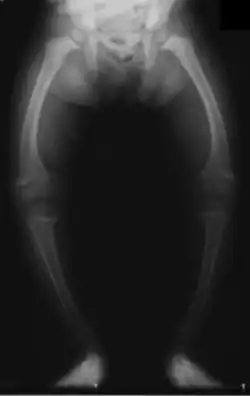

Kolana szpotawe (łac. genu varum) – wada kończyn dolnych polegająca na ustawieniu podudzia względem uda pod kątem otwartym do środka i wygięciu na zewnątrz trzonów kości udowej, piszczelowej i strzałkowej.

- odsunięcie od siebie kłykci przyśrodkowych na odległość powyżej 3 cm.